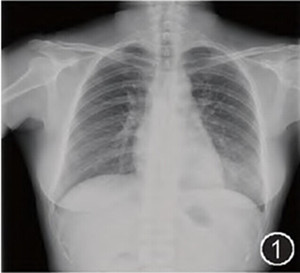

胸片有阴影,是肺结核?肺癌?

肺部阴影通常是指在透视中发现肺实质内有高密度区,在胸片上或CT上常表现为肿块或结节,一般肿块的标准是

体检结果里写着“肺部有阴影”,这意味着你的肺部可能有病变了,当然也像肺炎、肺脓肿、肺结核等拍胸片都

胸片肺部有阴影通常都是发生在现肺实质内有高密度区,通常情况下很有可能是属于肺部肿块还是结节。